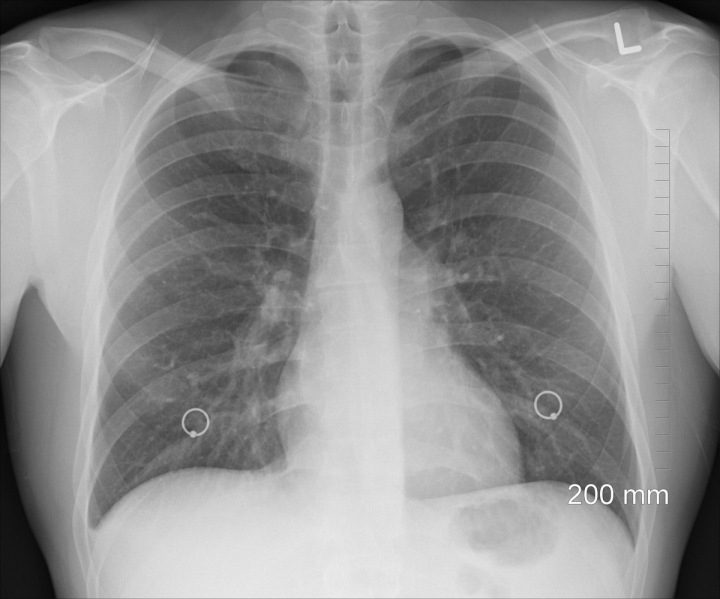

Nehovorím o koronavíruse. Kvôli nemu kašlete, až máte pocit, že si vykašlete pľúca, ako sa hovorí. Hovorím o prasknutí pľúc. Odborne sa tomu hovorí spontánny pneumotorax, čo znamená, že si proste jedna z polovíc pľúc, v horšom prípade vraj aj obe, z ničoho nič prasknú. To sa stalo tej mojej kamarátke. Ale tá to zistila až o tri dni… Dovtedy s tým normálne chodila a myslela si, že má obyčajnú chrípku sprevádzanú brutálnym kašľom. Keď po troch dňoch nevyšla schody do prvého poschodia, šla k doktorke. Tá ju chcela odbiť nejakými liekmi, ale vďakabohu si stála za svojím a doslova lekárku donútila urobiť jej röntgen pľúc. A hľa. Bol tam! Pľúca vyfúknuté ako balónik po ťažkej párty.

Rentgen plic.

Rentgen plic.Source: pixabay.com/oracast